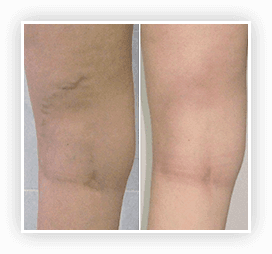

УНИКАЛЬНАЯ МНОГОКОМПОНЕНТНАЯ

МАЗЬ ОТ ВАРИКОЗА

Первые результаты заметны на второй неделе. Окончательный результат - через 2 месяца. Повторный курс можно пройти через месяц.